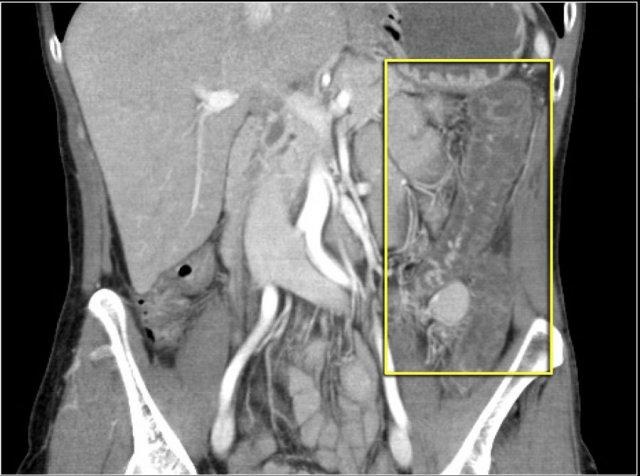

Tăng áp lực tĩnh mạch cửa

Tăng áp lực tĩnh mạch cửa là một nguyên nhân khác gây ra dấu hiệu bia nước.

Khi bệnh nhân bị tăng áp lực tĩnh mạch cửa, áp lực tăng cao sẽ được truyền đến đại tràng phải.

Điều này dẫn đến sự sản sinh các chất trung gian gây viêm và tăng sản xuất nitric oxide, gây tổn thương mô.

Hậu quả là xuất hiện viêm đại tràng khu trú ở bên phải.

Hãy phân tích các hình ảnh trước khi tiếp tục đọc.

Các dấu hiệu bao gồm:

- Xơ gan – bờ gan không đều

- Giãn tĩnh mạch và lách to

- Cổ trướng

- Viêm đại tràng bên phải

- Phình động mạch gan

Viêm đại tràng bên phải ở bệnh nhân xơ gan và tăng áp lực tĩnh mạch cửa. Hình ảnh nội soi là của bệnh nhân khác có viêm đại tràng bên phải.